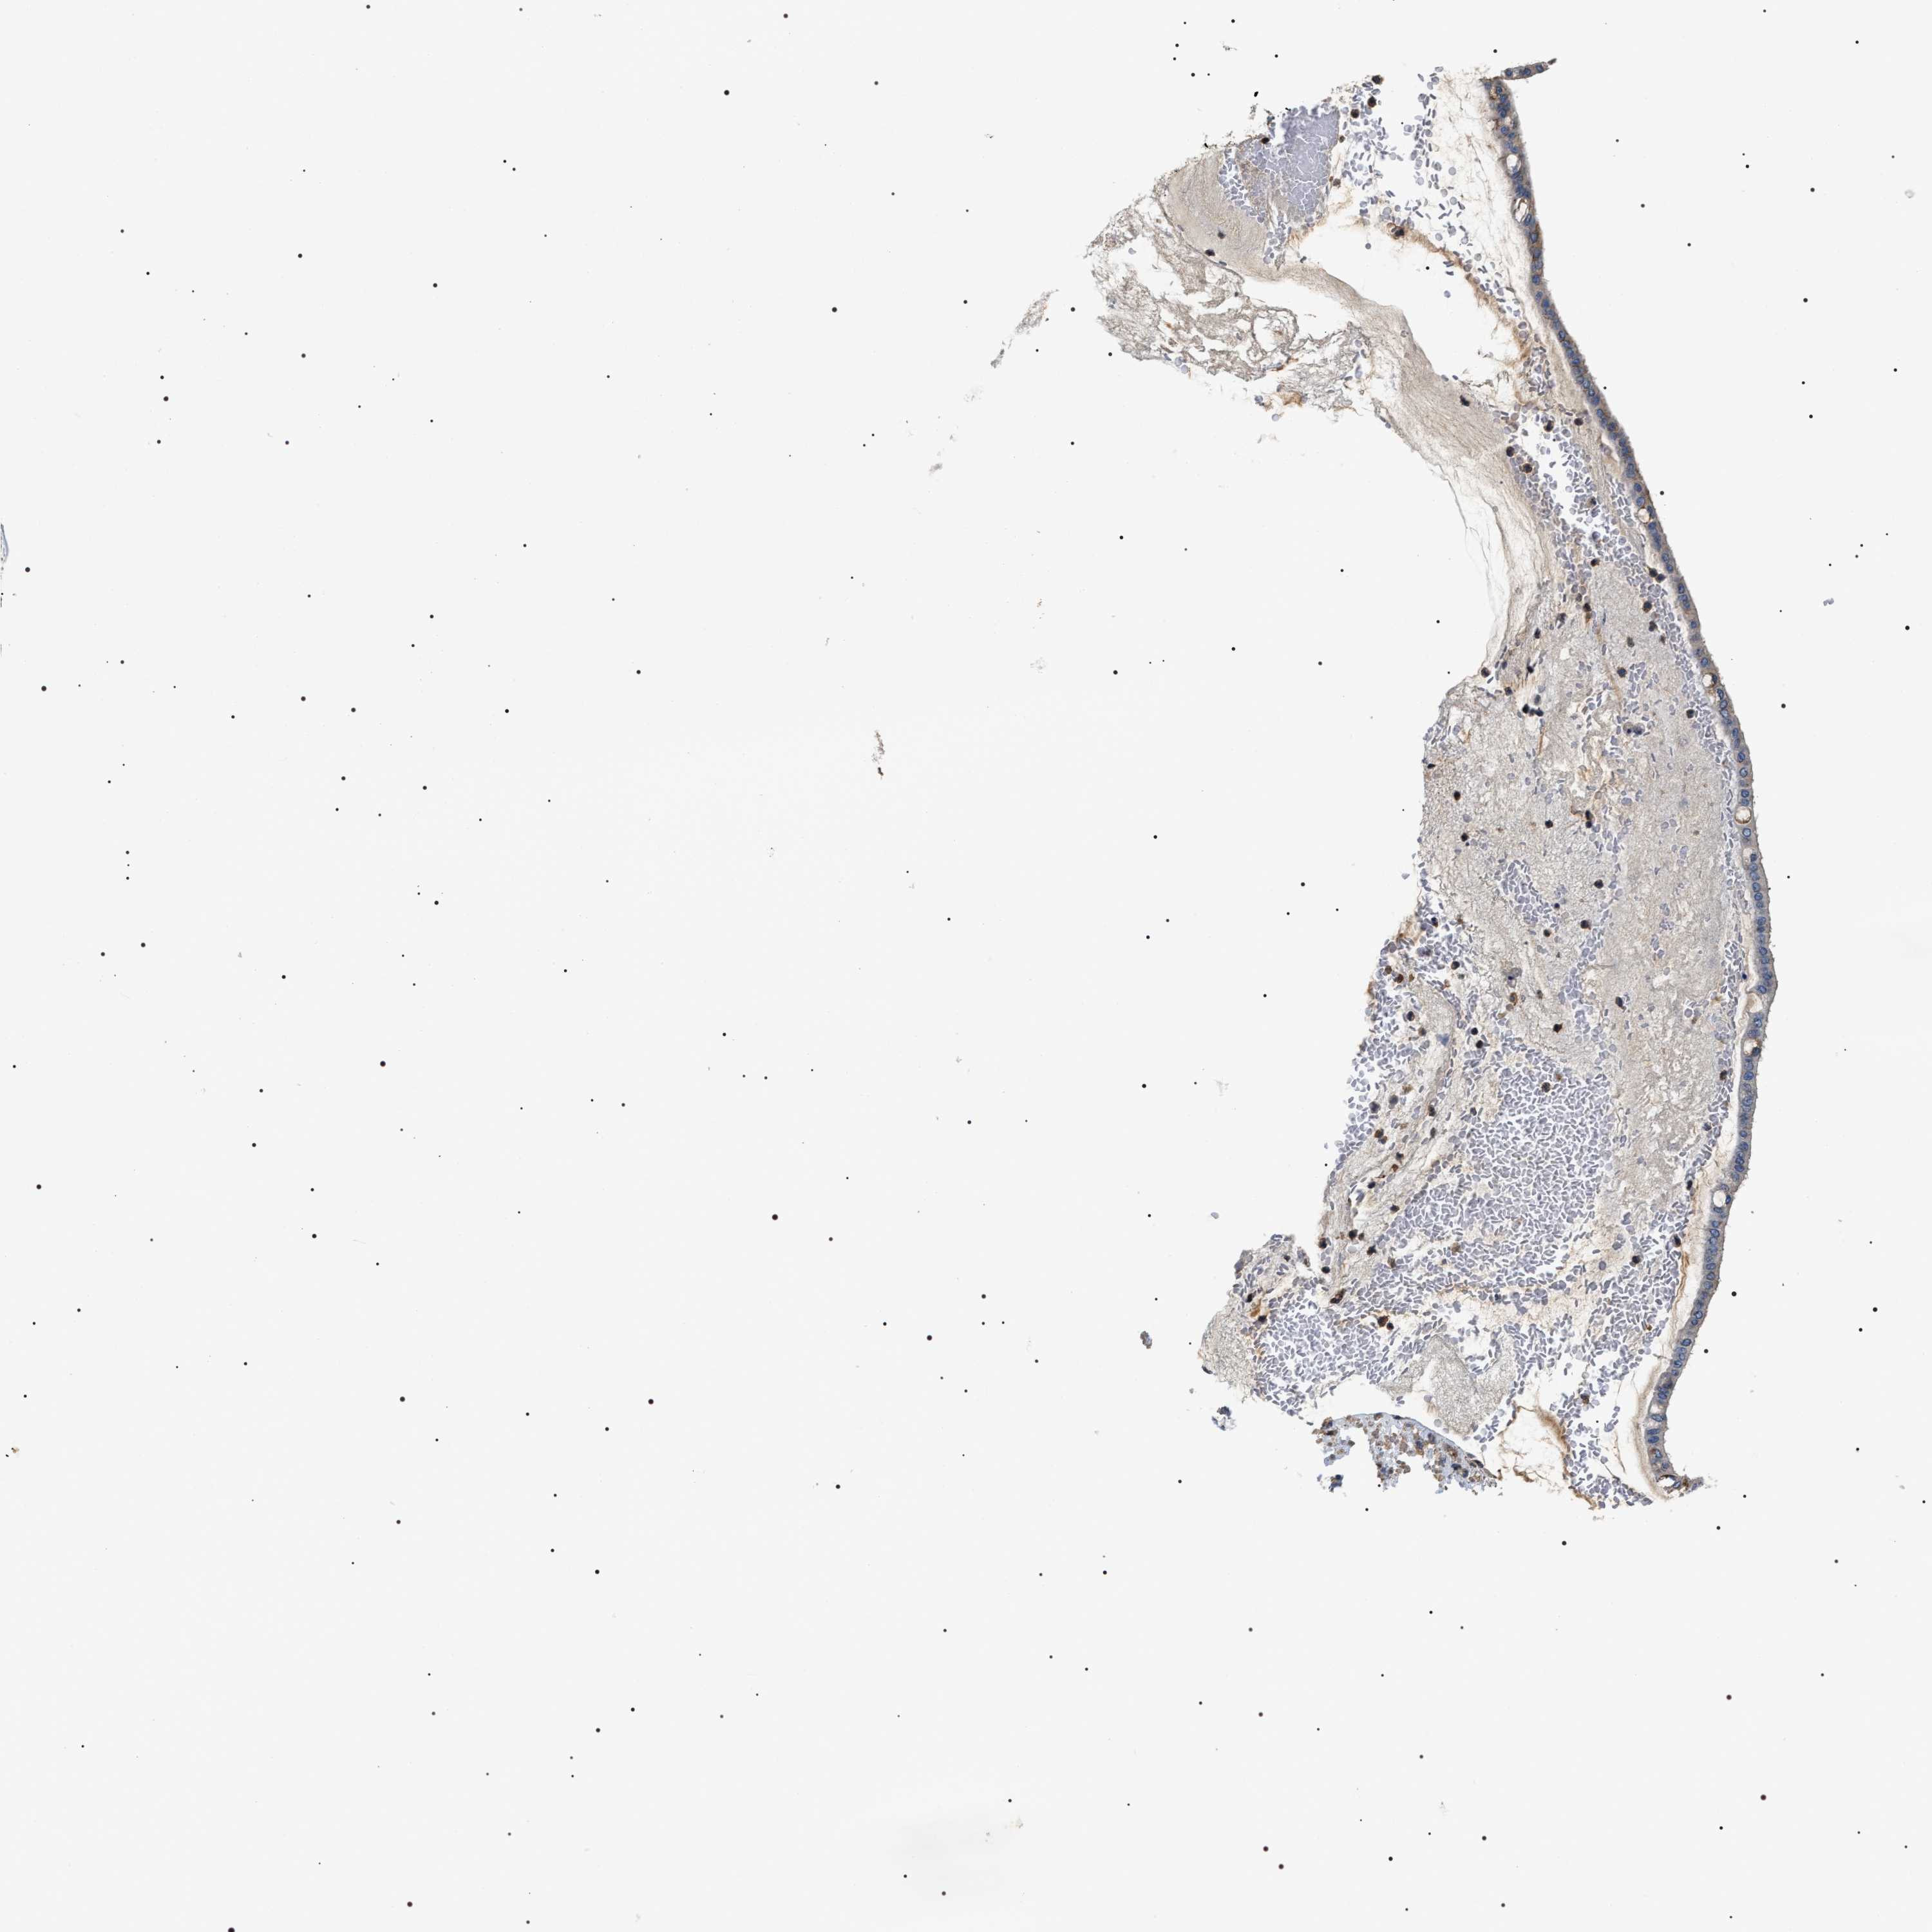

OVARIAN CANCER - Protein expressioni

A mouse-over function shows sample information and annotation data. Click on an image to view it in a full screen mode. Samples can be filtered based on level of antibody staining by selecting one or several of the following categories: high, medium, low and not detected. The assay and annotation is described here.

Note that samples used for immunohistochemistry by the Human Protein Atlas do not correspond to samples in the TCGA dataset.

Antibody stainingi

Antibody staining in the annotated cell types in the current human tissue is reported as not detected, low, medium, or high, based on conventional immunohistochemistry profiling in selected tissues. This score is based on the combination of the staining intensity and fraction of stained cells.

Each image is clickable and will lead to virtual microscopy that enables deeper exploration of all samples and also displays staining intensity scores, fraction scores and subcellular localization as well as patient and tissue information for each sample.

Antibody HPA020386

Staining

Cystadenocarcinoma, serous, NOS

Carcinoma, endometroid

Cystadenocarcinoma, mucinous, NOS

Carcinoma, NOS